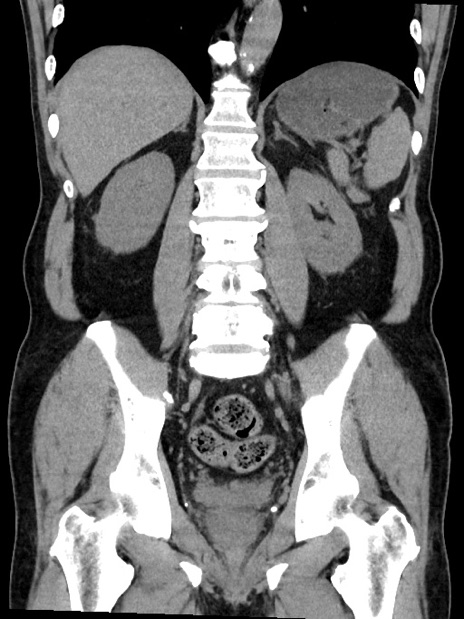

症例35(冠状断像)

【症例】70歳代 男性

【主訴】腹部膨満、嘔吐

【現病歴】昨日より腹部膨満感出現。本日増悪し、仙痛出現。嘔吐あり、受診。

【既往歴】糖尿病、胆摘後

【身体所見】BP 149/80mmHg、HR 74/min、BT 35.9℃、腹部:膨満、軟、圧痛なし。腸雑音減弱あり。上腹部正中切開瘢痕あり。

【データ】WBC 13500、CRP 1.72